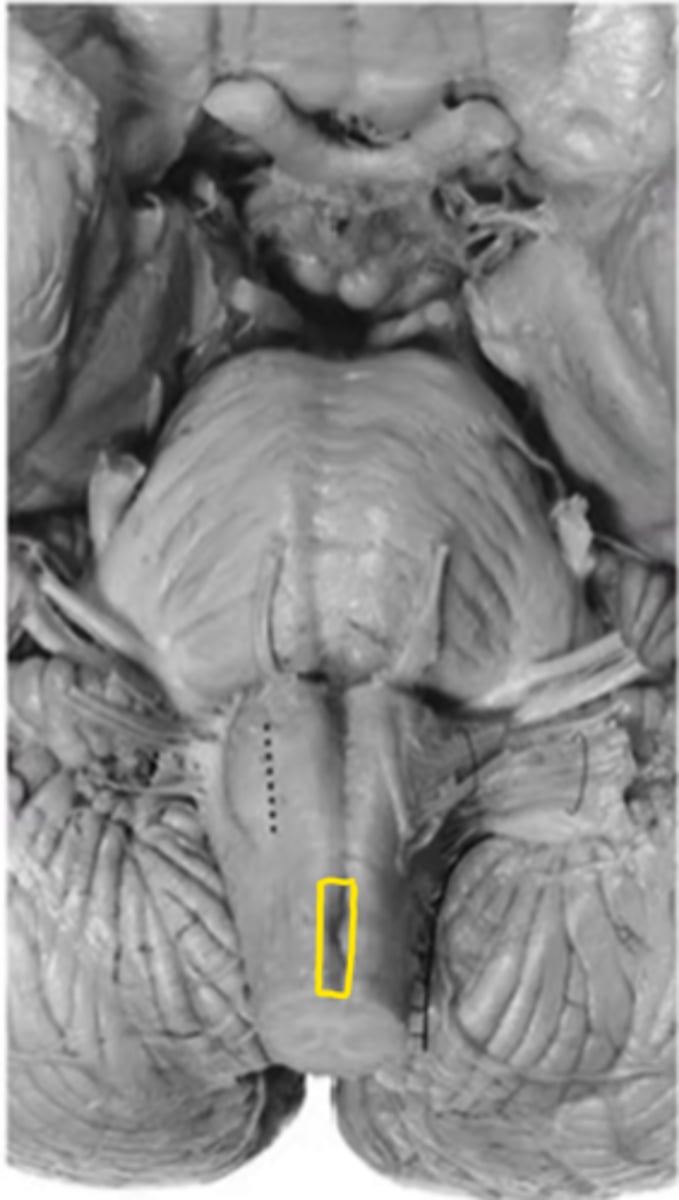

olive

ID the structure

pre-olivary sulcus

principle olivary nucleus

closed medulla

ID the brainstem level